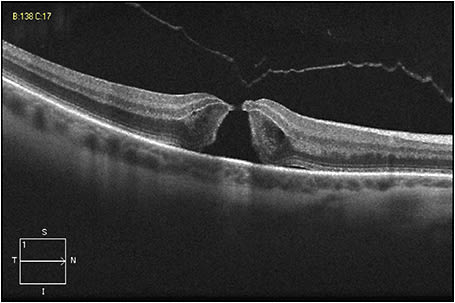

Figure 1 shows an eye in this series, with FTMH measuring 216 µm and concurrent focal VMT; this patient’s best-corrected Snellen VA was 20/70. Figure 2 shows VMT release following intravitreal ocriplasmin, with a decrease in VA to 20/200 at one week following injection. Figure 3 demonstrates an increase in FTMH size (now measuring 264 µm) at 12 days following injection.

Figure 1. An eye from the series at the New England Eye Center, with FTMH measuring 216 µm and concurrent focal VMT; this patient’s best-corrected Snellen visual acuity was 20/70.